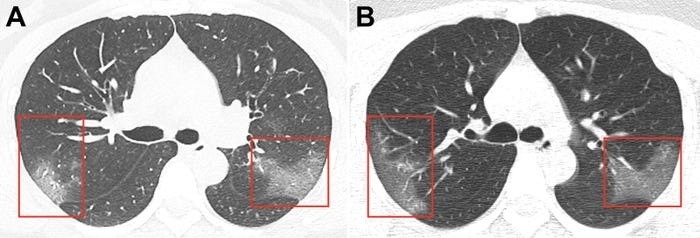

Hình ảnh phổi của bệnh nhân bị virus corona phá hủy

Kết quả chụp CT phổi của các bệnh nhân Covid-19 thường chung đặc điểm là xuất hiện những đốm trắng.